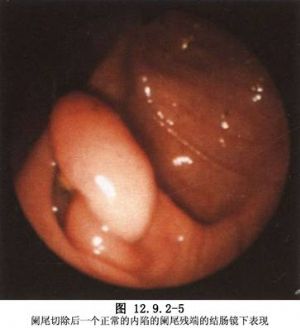

(4)从10mm套管内取出阑尾,如阑尾炎症重或穿孔不宜直接取出,将其放入取物套内取出。取阑尾时应在监视镜下操作(图12.9.2-5)。